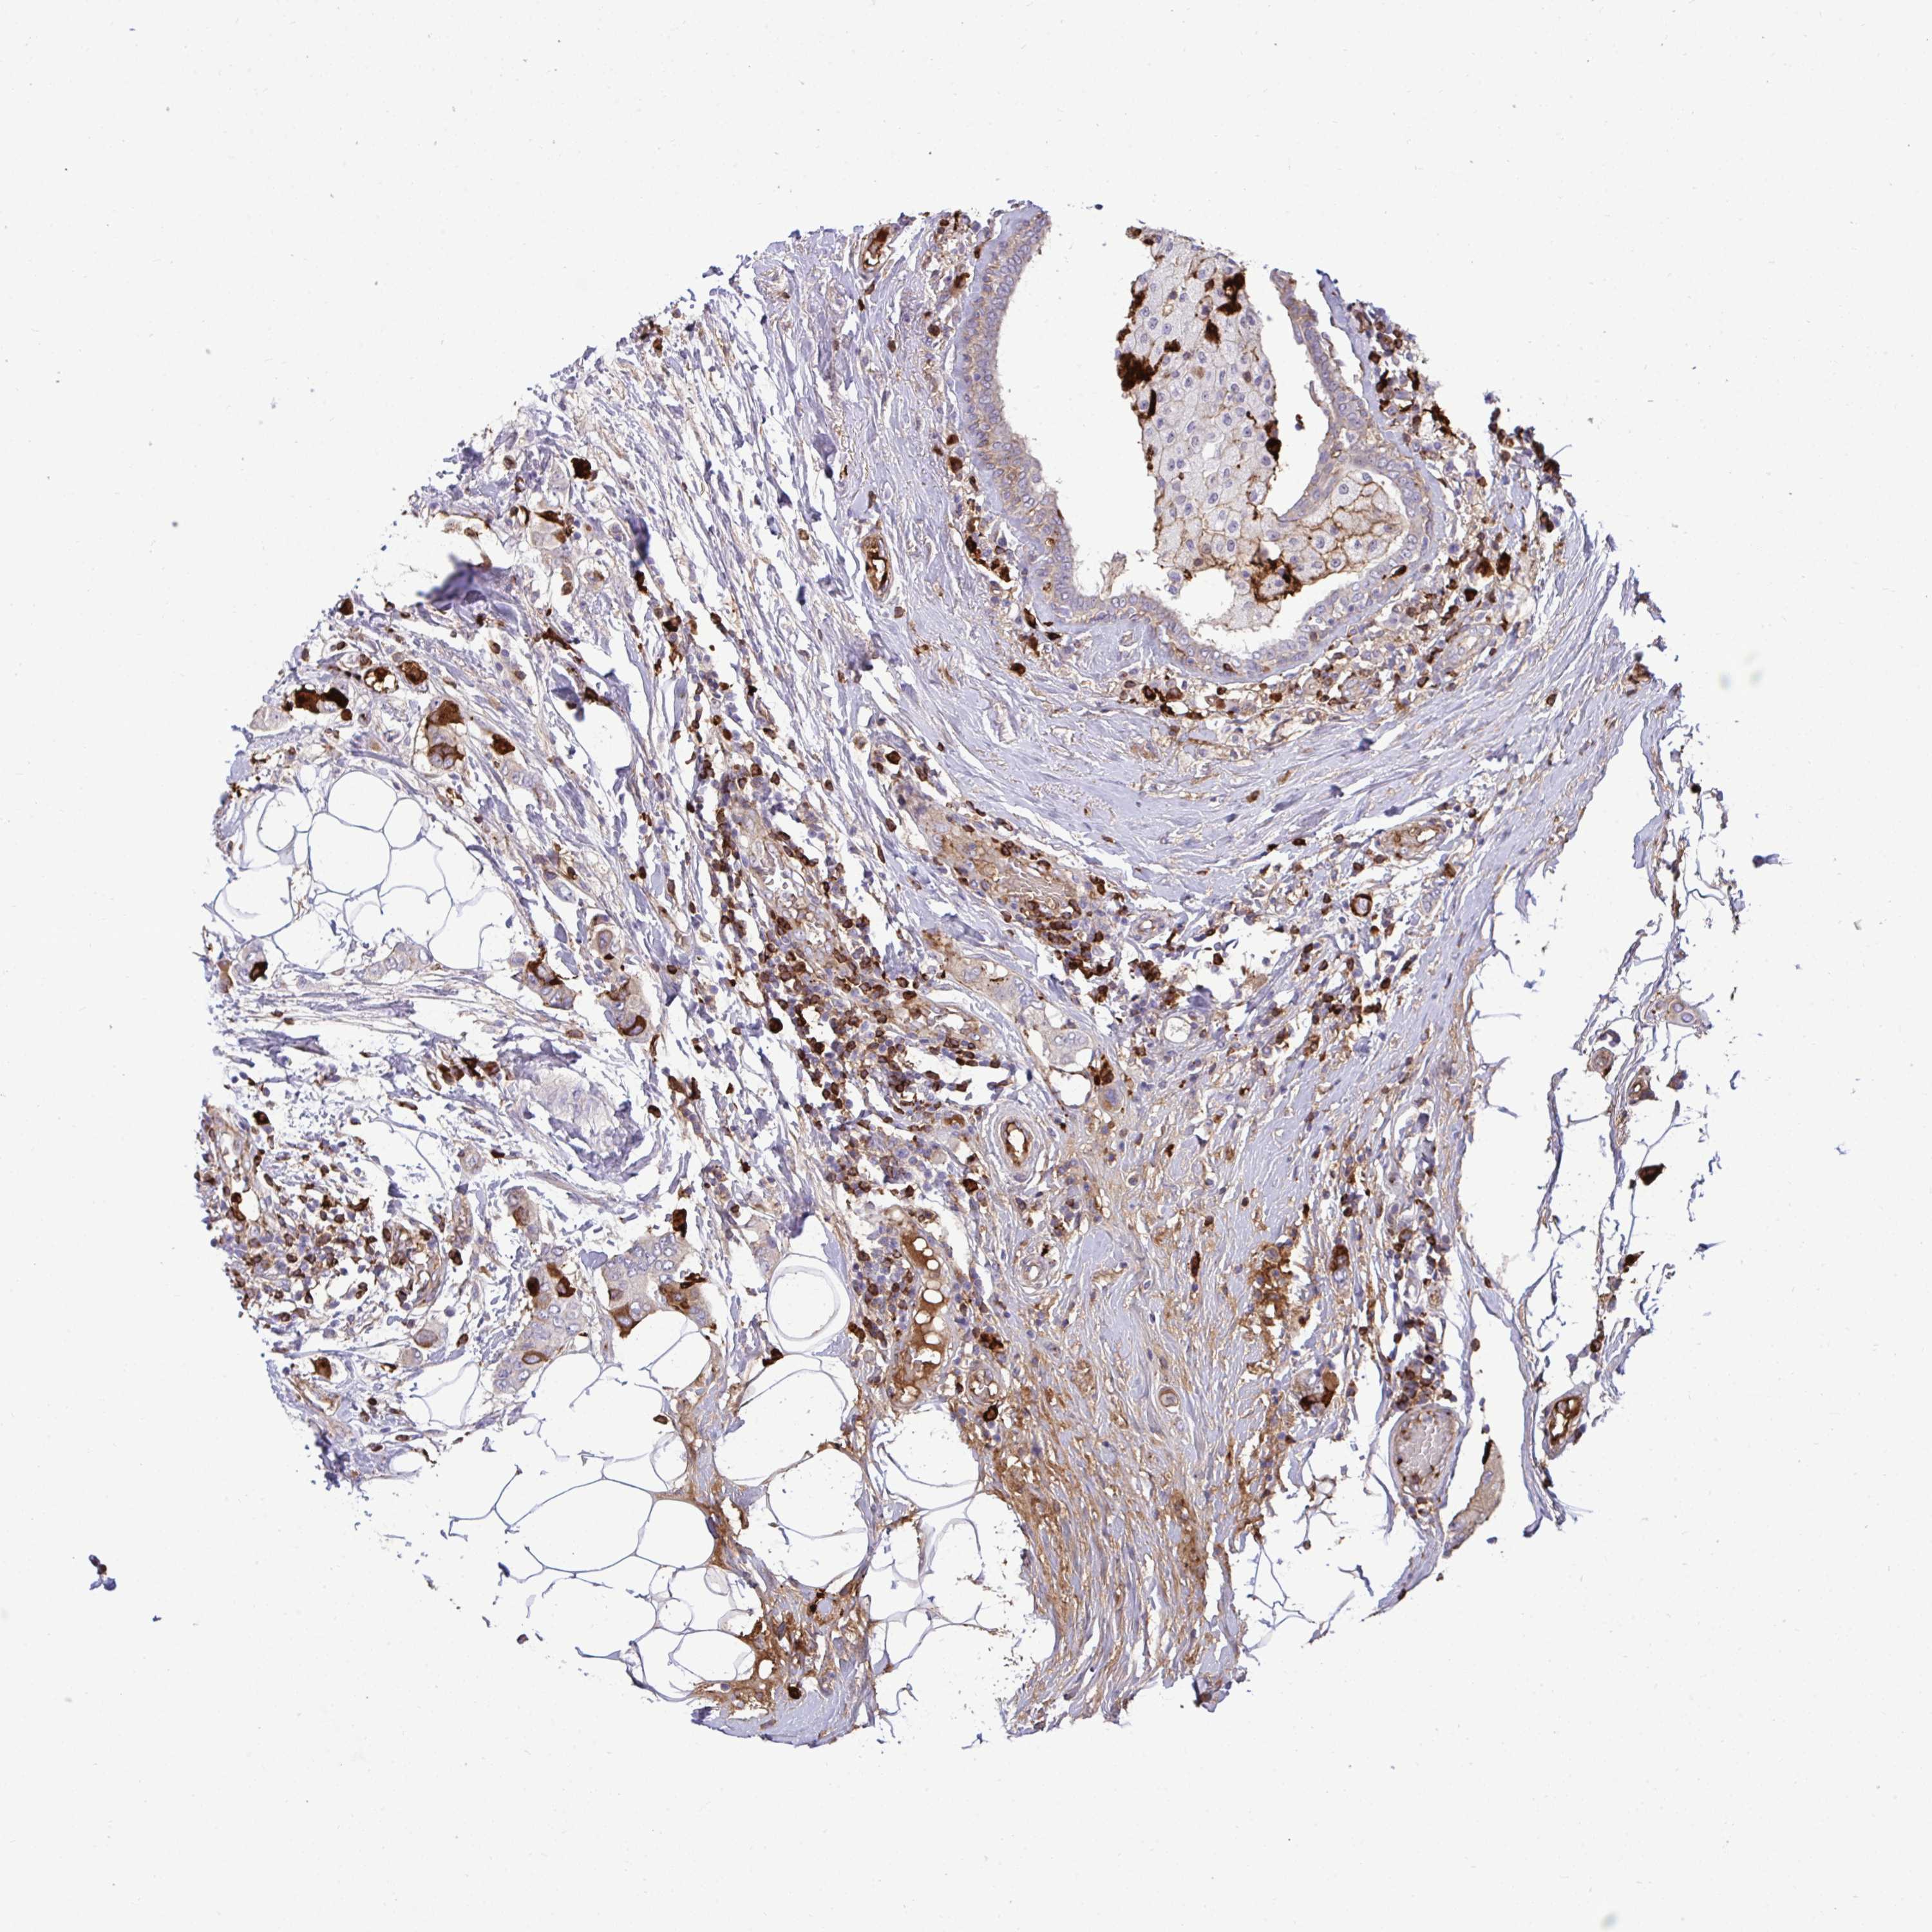

CANCER BREAST CANCER Show tissue menu

BRCA TCGA BRCA VALIDATION PROTEIN EXPRESSION